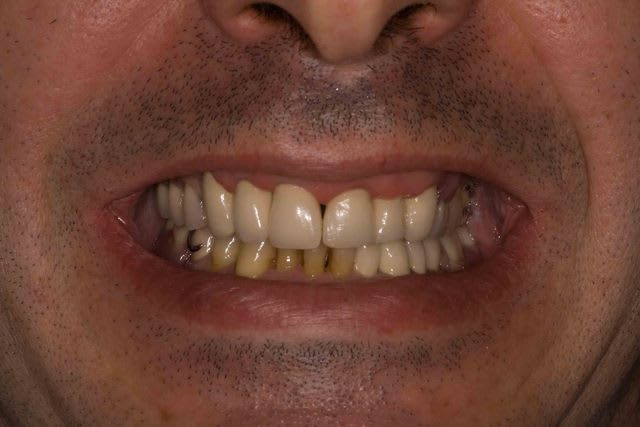

Mais la, apres 1 an de traitements reguliers, entre les lambeaux d'assainissements, les élongations coronaires et les reprises de traitements pourrave j'ai enfin BOUCLE CE CAS !

A l'origine le patient ne voulait surtout pas touché aux dents encore " saine" car il les trouvait bien.

Maintenant il les trouve jaunes et veux les blanchir. Comme quoi un nouveau sourire amene souvent un nouveau regard.

La fin.

Spéciale kassededi à cyril couscous